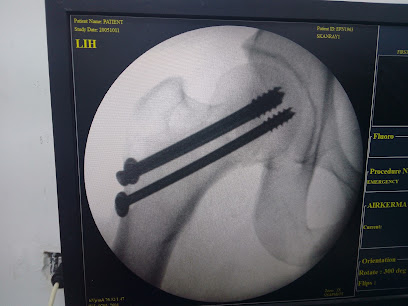

د. محمد سمير البديوي لجراحة العظام و العمود الفقري orthopaedic surgery clinic

د. محمد سمير البديوي يقدم خدمات جراحة العظام والعمود الفقري في عيادته. يمكنك التواصل مع العيادة عبر الهاتف على 01021527044 لتحديد مواعيد الزيارة والاستفسار عن خدماتها.